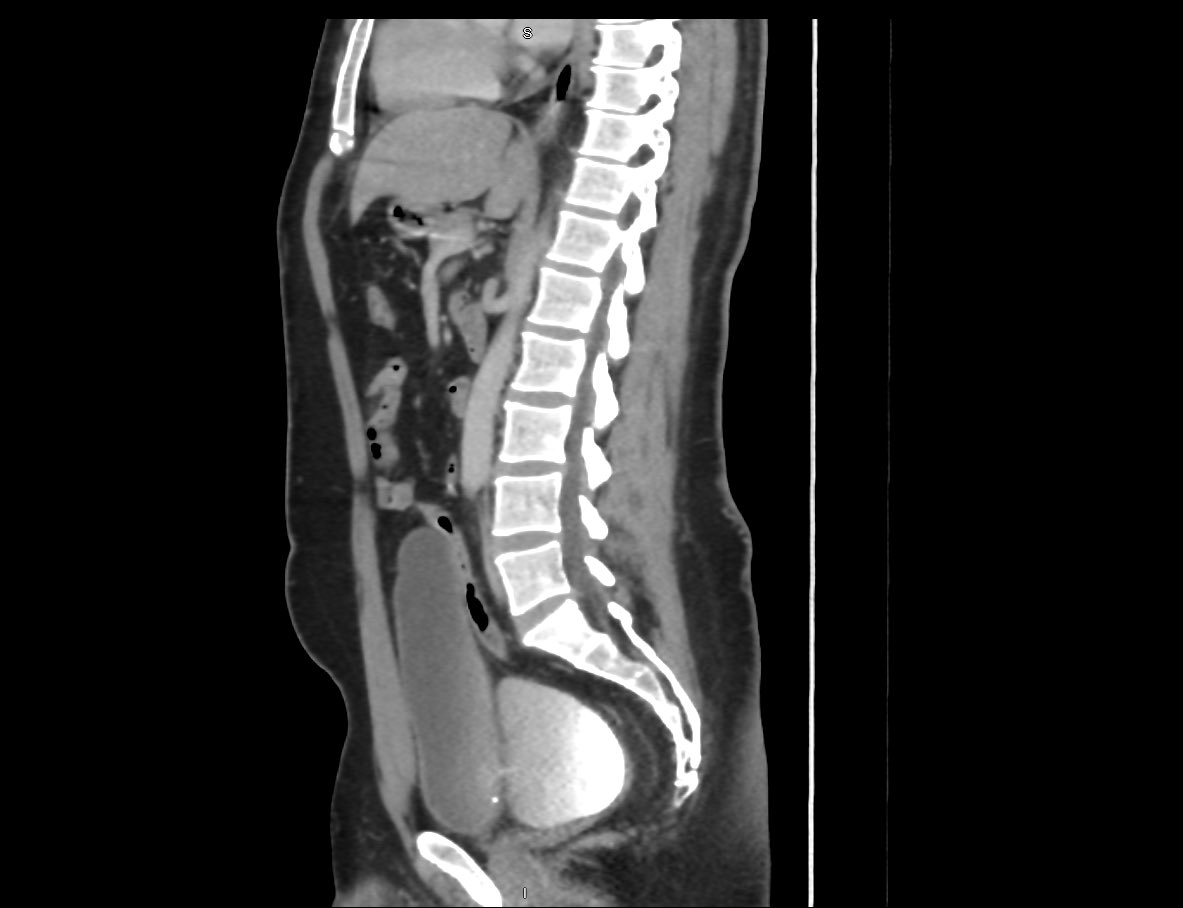

Together with @MAlKhameesMD we’ve adopted #Retzius_sparing #robotic #prostatectomy as our standard approach for the past year, every case at @NGHAnews has followed this technique.

This is a 53 y/o with intermediate-risk prostate cancer

•Bilateral intrafascial nerve-sparing

•Negative margins

•Catheter out on day 5

•Continent after catheter removal (zero pads)

•Erectile function preserved

Retzius-sparing offers earlier continence and better functional recovery without compromising oncological outcomes.